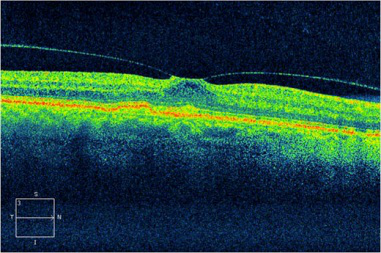

(OCT查驗顯示信息雙眼的黃斑前膜,化學纖維膜在黃斑表層造成伸展的能量,可導致黃斑浮腫或孔裂,導致視線中間出現冷色)